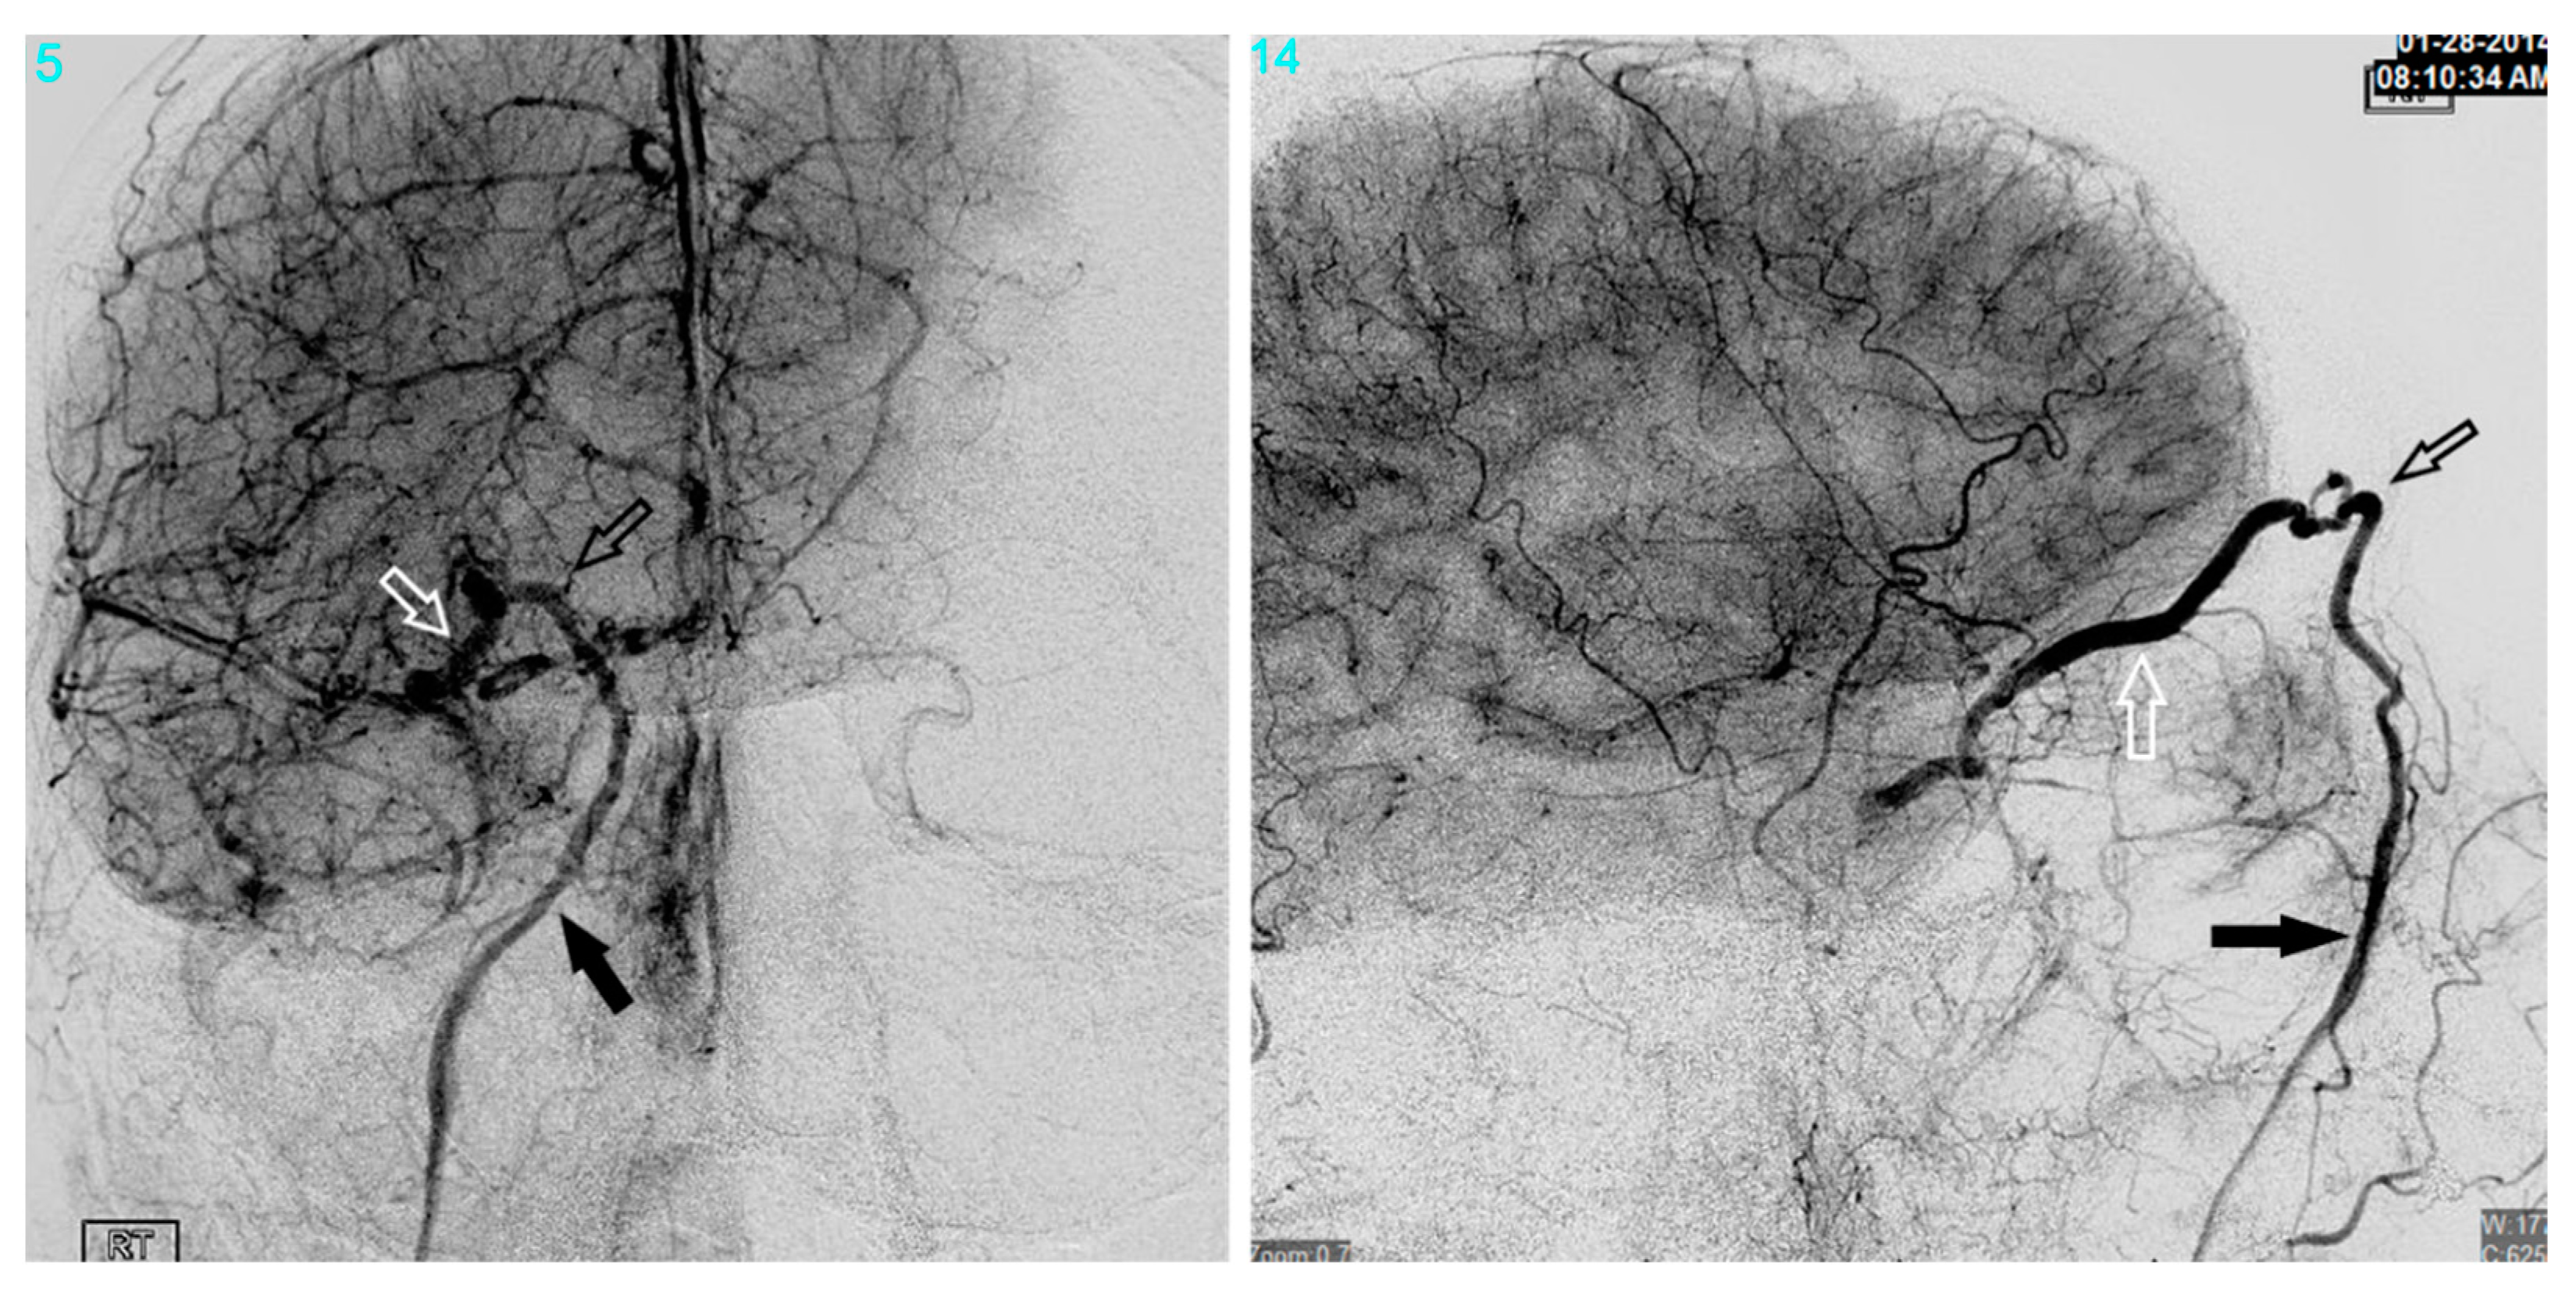

Figure 10. Demonstrates a right sided direct carotid cavernous fistulas (CCF). An occlusion balloon is placed within the right cavernous internal carotid artery (ICA) (white arrow) across the fistula site. Coils are placed within the intercavernous sinus (black solid arrow) through a transvenous inferior petrosal sinus (IPS) approach (white solid arrow). Note the superior petrosal sinus (black arrows), in the lateral projection, with its acute angle off the transverse sinus.